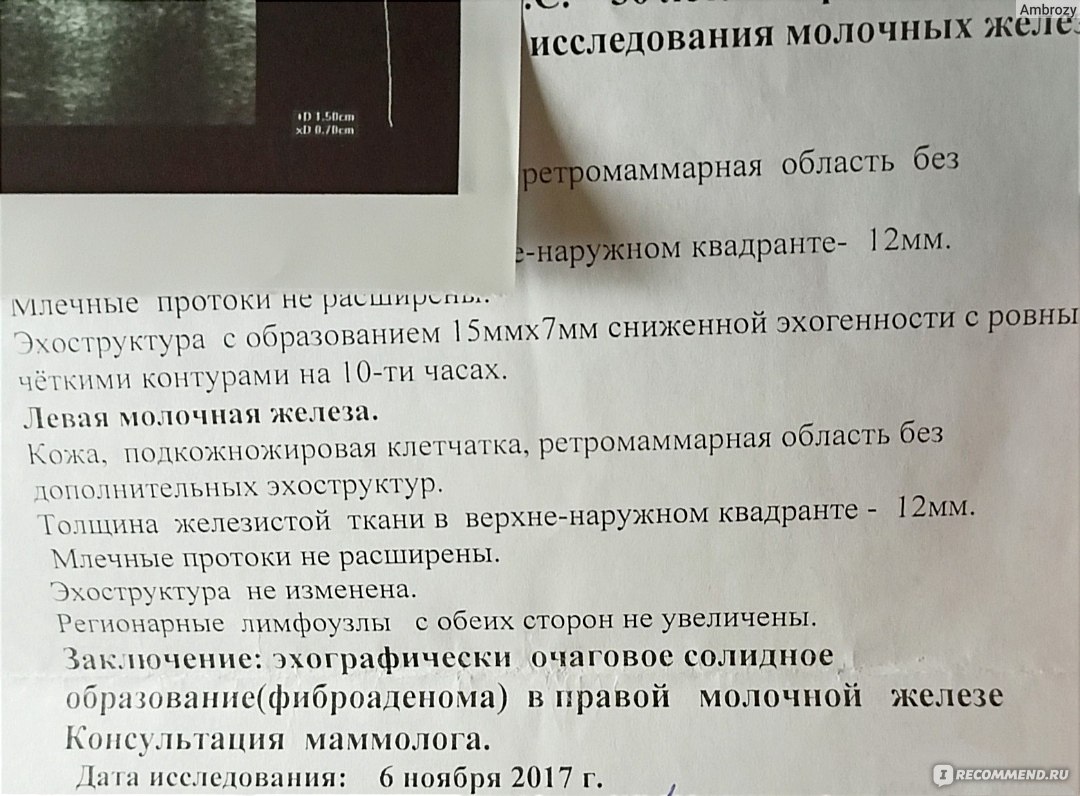

Фиброзно-кистозная мастопатия на УЗИ